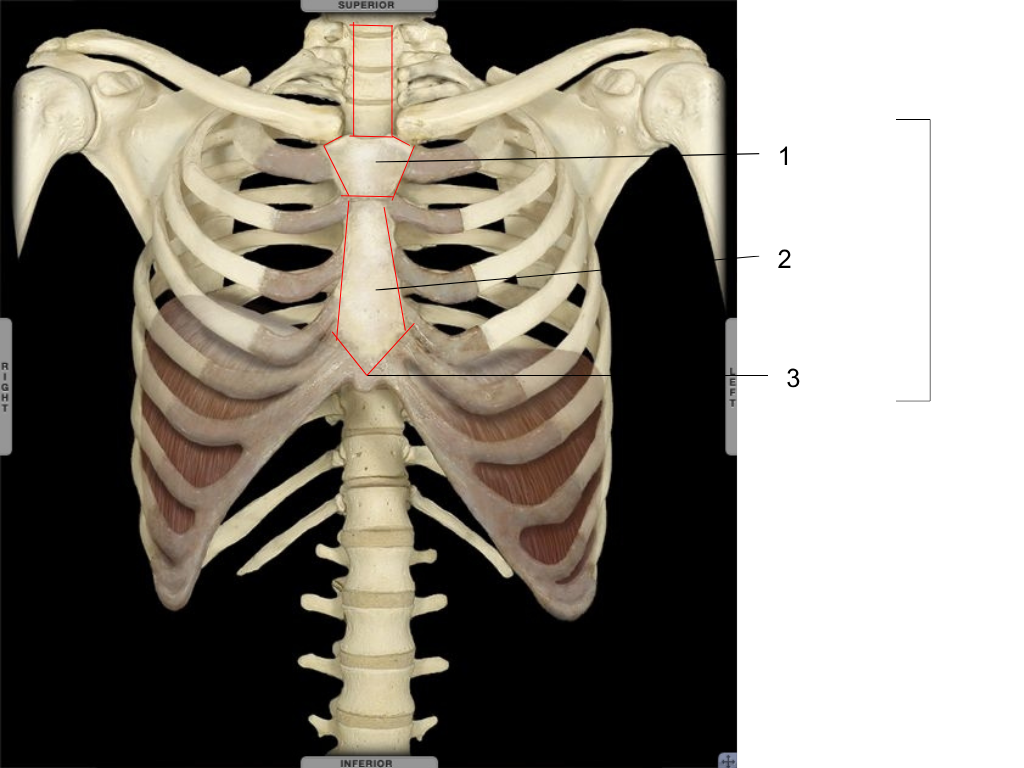

manubrium

what is #1 pointing at?

gladius

what is #2 pointing at?

xiphoid

what is #3 pointing at?

first 7

where are the true ribs located?

last 5

where are the false ribs located?

2 of the last false ribs

where are floating ribs located?